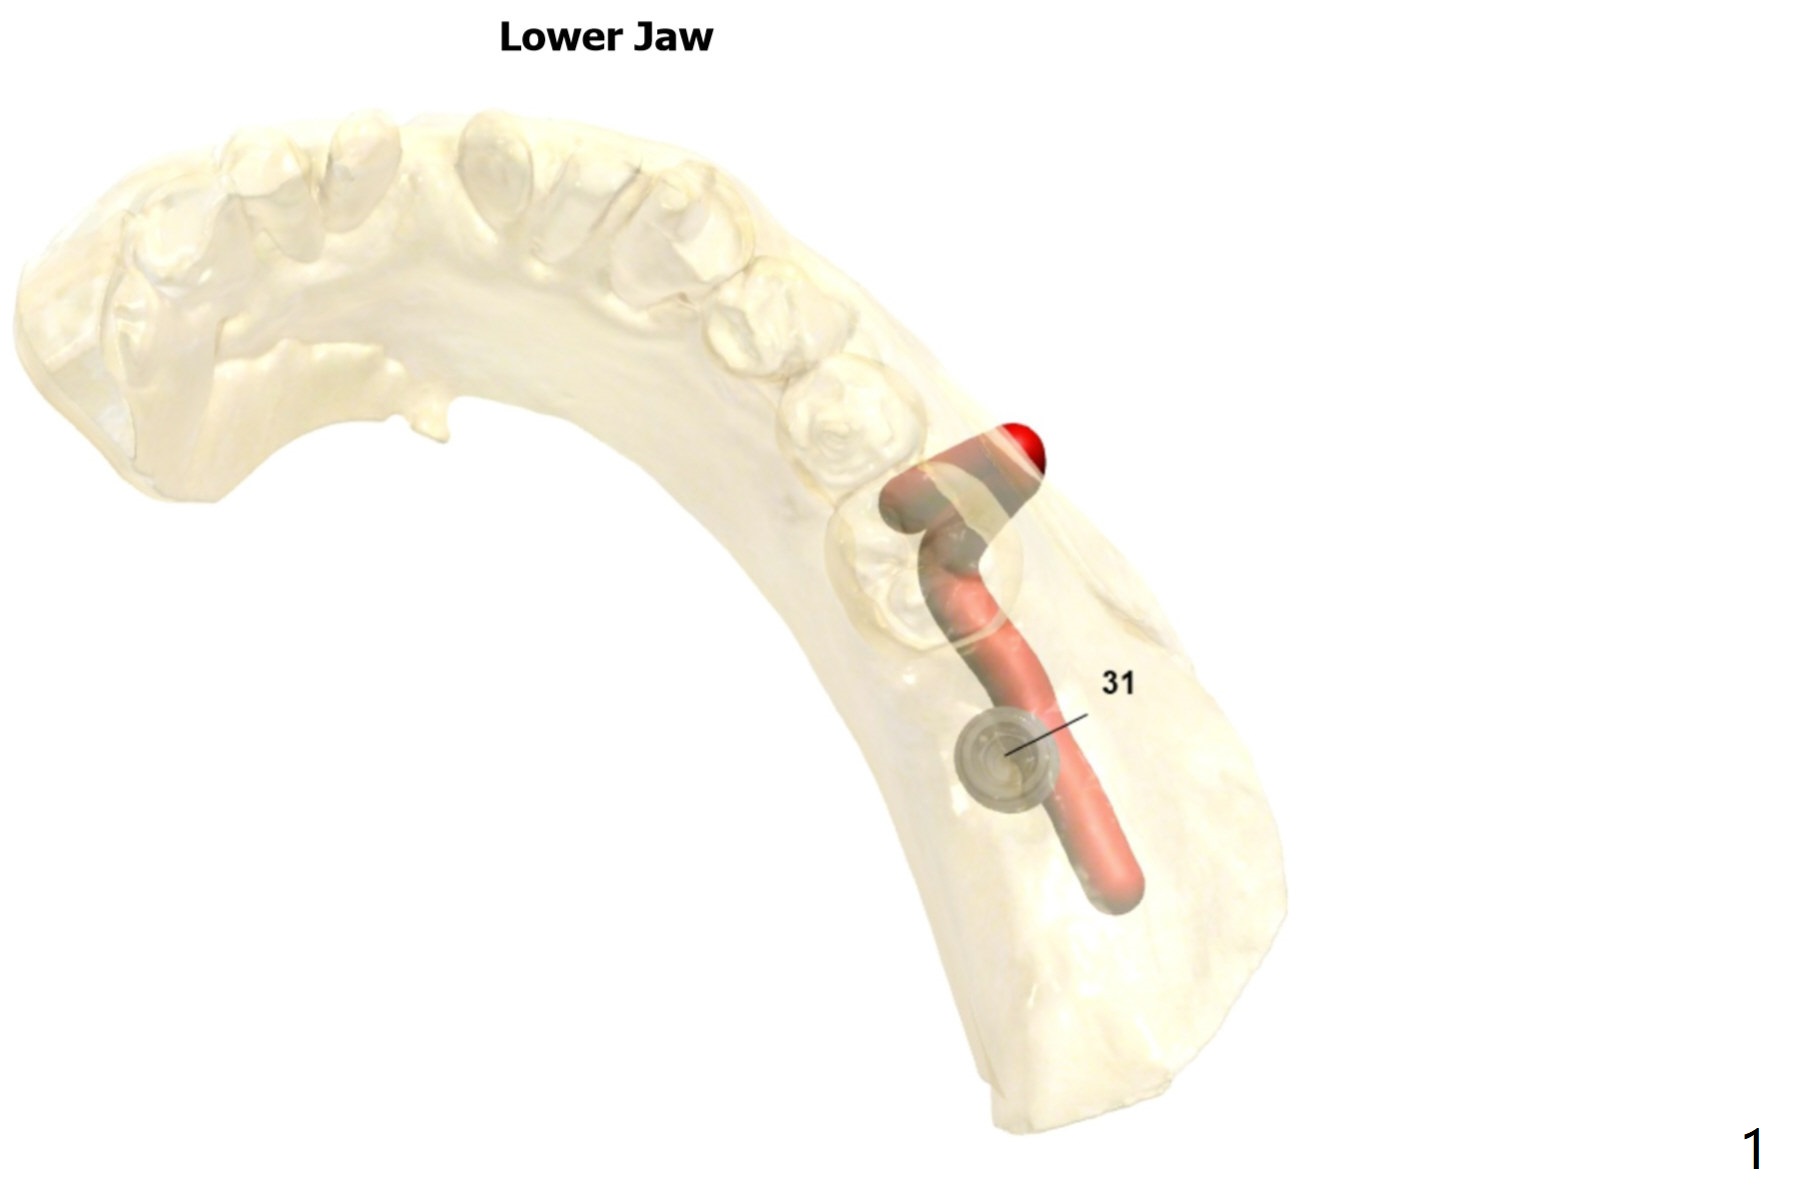

Guided surgery will be scheduled 6 months post socket preservation at #31 (Fig.1). The bone density is low buccal to the recipient site (Fig.2). Either bone expansion should be done prior to implant placement or bone graft is needed post placement (Fig.3). Use Implant Cassette and #15 may be utilized to check whether bone graft is needed. Before soak the guide, check it against the lower model to see whether acrylic clearance is necessary for bone expansion. After 2.2x7.3 mm drill, use 2.2x8.5 and 2.2x10 mm ones (Fig.5). Switch to #2 bone expander (1.3/2.3 mm) and take PA to confirm the depth. Measure the length of the last drill and #2 expander beforehand. Continue bone expanders until #5 (3.0/4.4 mm). Expect less depth as the # of expanders increases.